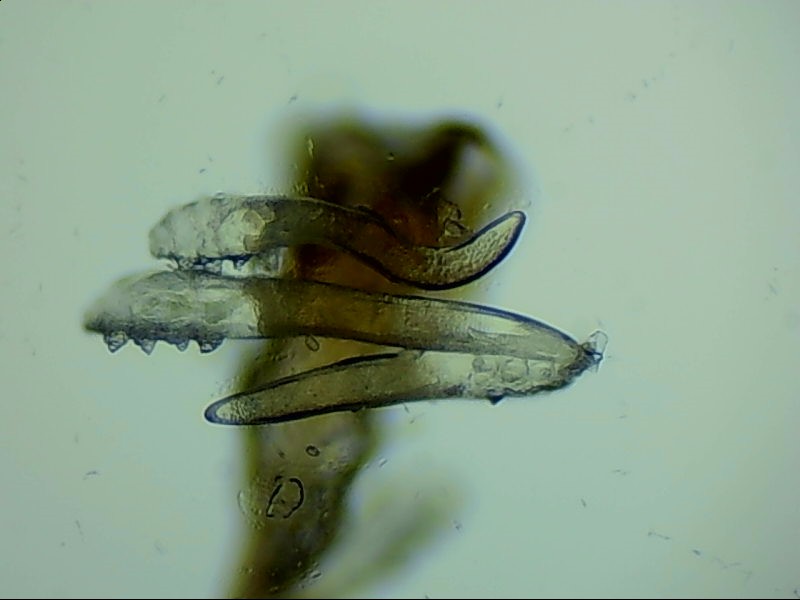

蠕形螨是螨蟲的一種,主要寄居在毛囊中。蠕形螨以分泌的油脂、分泌物為食,所以眼部寄居著蠕形螨的患者多有亂睫或睫毛脫落的癥狀。

蠕形螨寄居后,它們以睫毛毛囊里面的油脂為食。隨著油脂的缺失,睫毛會長的東倒西歪,如果毛囊里的油脂都被吃光了,就會出現(xiàn)睫毛脫落這種蠕形螨性瞼緣炎的典型癥狀。

身體健康時,蠕形螨就吃吃油脂,夜里爬出來活動、交配,與我們相安無事,一旦身體的免疫力下降,蠕形螨的活動、產(chǎn)的卵、排泄的廢物和分泌的分泌物都會引起過敏反應(yīng)?;颊邥霈F(xiàn)眼癢、異物感、眼干、瞼緣充血、鱗屑、睫毛根部袖套狀分泌物及睫毛脫落等癥狀,嚴(yán)重者可并發(fā)結(jié)膜及角膜病變,給生活帶來不便和困擾。